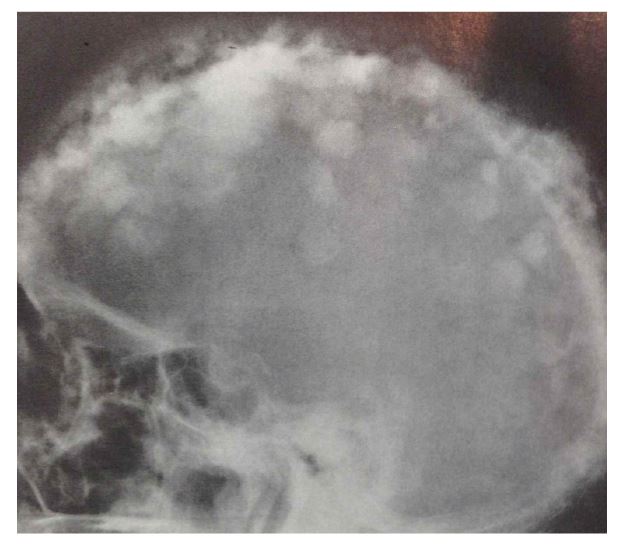

Xray: 코튼 울(cotton wool) 형태의 국소경화 19

b465aad5018c55d0068628177576c60b_1716172700_5925.JPG

그림 머리뼈에 나타난 코튼 올